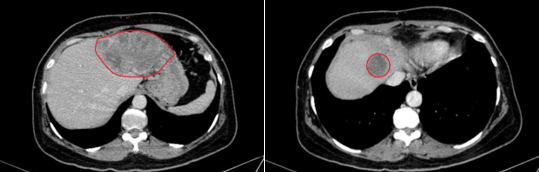

Hình ảnh chụp cắt lớp vi tính sau 3 chu kỳ điều trị hóa chất: gan biến đổi hình thái, bờ không đều, phì đại hạ phân thùy 1. Nhu mô đồng nhất trước và sau tiêm thuốc cản quang. Vị trí hạ phân thùy 2,3,4,8 có các khối tổn thương kích thước lớn nhất 97x67mm, trước tiêm giảm tỷ trọng, sau tiêm ngấm thuốc kém, nhấm viền ngoại vi, xâm lấn gây huyết khối nhánh trái tĩnh mạch cửa.

Hình 2. Vị trí hạ phân thùy 2,3,4,8 có các khối tổn thương kích thước lớn nhất 97x67mm, trước tiêm giảm tỷ trọng, sau tiêm ngấm thuốc kém, nhấm viền ngoại vi( viền màu đỏ)

NHẬN XÉT: Sau 3 đợt điều trị, kích thước khối u giảm một phần (khối lớn nhất có kích thước 120x67mm giảm xuống còn 97x67mm) cho thấy có đáp ứng sau điều trị, chỉ số CA19-9 được duy trì ổn định trong giới hạn bình thường cho thấy không có dấu hiệu tăng sinh tiến triển của khối u, chức năng gan được bảo tổn sau 3 đợt điều trị. Điều này cho thấy phương pháp điều trị đang giúp kiểm soát tình trạng bệnh một cách hiệu quả, mang lại hy vọng tích cực cho quá trình điều trị tiếp theo.